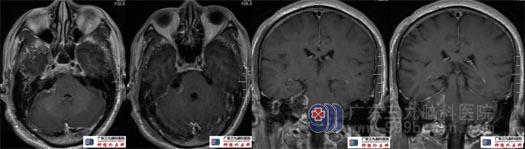

术后复查头颅MRI示肿瘤切除满意。